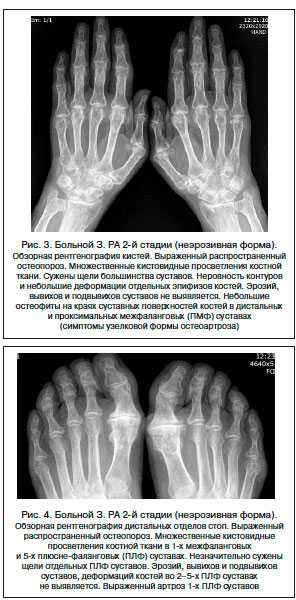

На снимке хорошо видно истончение хрящевых тканей, костей и сужение суставных щелей, выявляются эрозии. Чаще всего эрозийные поражения видны около локтевой кости, в области запястья, на фалангах, у хряща.